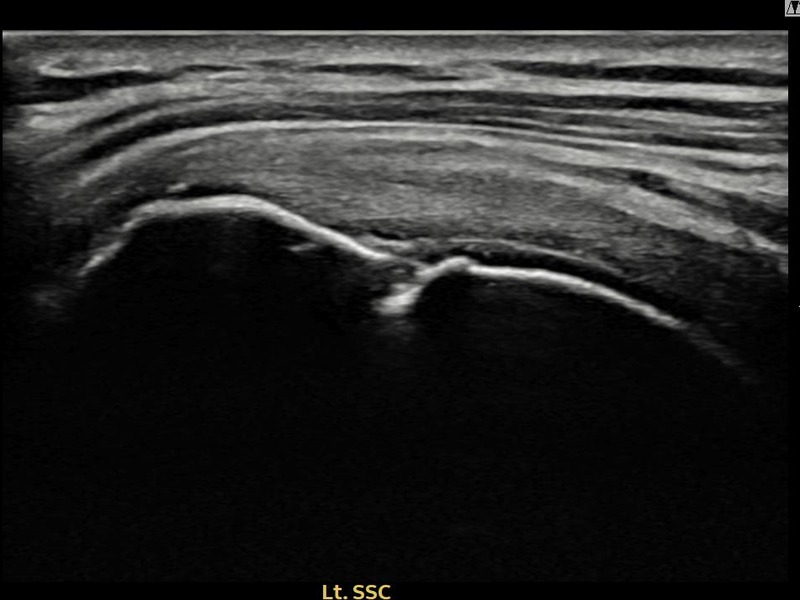

서ㅇㅇ님 · 좌측 극상근건 관절면측 부분파열

좌측 어깨 통증으로 팔을 올리기 불편하여 내원하셨습니다. 초음파 검사에서 관절면측 극상근건 부분파열이 확인되었으며, 어깨인대 축소봉합술 후 파열 부위 연속성이 회복되었습니다.

서ㅇㅇ님 · 좌측 극상근건 부착부 부분파열

좌측 어깨 부착부 통증과 야간 통증으로 수면 장애가 있어 내원하셨습니다. 초음파 검사에서 극상근건 부착부 부분파열이 확인되었으며, 어깨인대 축소봉합술 후 부착부 힘줄이 구조적으로 회복되었습니다.